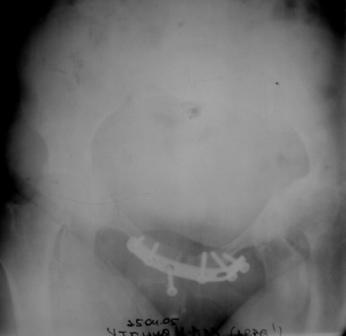

Уважаемые коллеги! Пациентка 32 года с застарелым повреждением таза, после остеосинеза лонного сочленения пластиной. Посоветуйте с выбором тактики и методик лечения.

На 7 сутки

Получила травму в феврале 2004г в г.Лобытнанги ЯНАО Тюм.обл. Через неделю после поступления выполнен остеосинтез лонного сочленения пластиной. 1,5 месяца на скелетном вытяжении. В последующем ходит при помощи костылей с нагрузкой на правую ногу. Имеется нестабильность половин таза, неправильно-консолидированный перелом левой вертлужной впадины, невропатия седалищного нерва слева. В результате невропатии седалищного нерва сформировалась эквинусная установка левой стопы,парестезии по подошвенной поверхности.

Клинически: ходит на костылях с нагрузкой на правую ногу. Левая стопа в эквинусе. Осевая нагрузка на левую н\конечность болезненна в области левого тазобедренного сустава, при прикосновениях к подошвенной поверхности стопы у пациентки чувство зжения. В левом коленном суставе полный обьем движений, в левом тазобедренном резко ограничено отведение и ротация, укорочение левой н\конечности на 2,5 см. При полипроекционной и функциональной Р-графии выявлена нестабильность левого КПС и лонного сочленения, консолидированный в порочном положении поперечный оскольчатый перелом левой вертлужной впадины с центральным смещением головки бедра. Нами выполнена коррекция деформации левой стопы. Планируется выполнить введение 2 канюлированных илиосакральных винтов слева, реостеосинтез лонного сочленения реконструктивной пластиной, после заживления ран - тотальное эндопротезирование левого тазобедренного сустава.